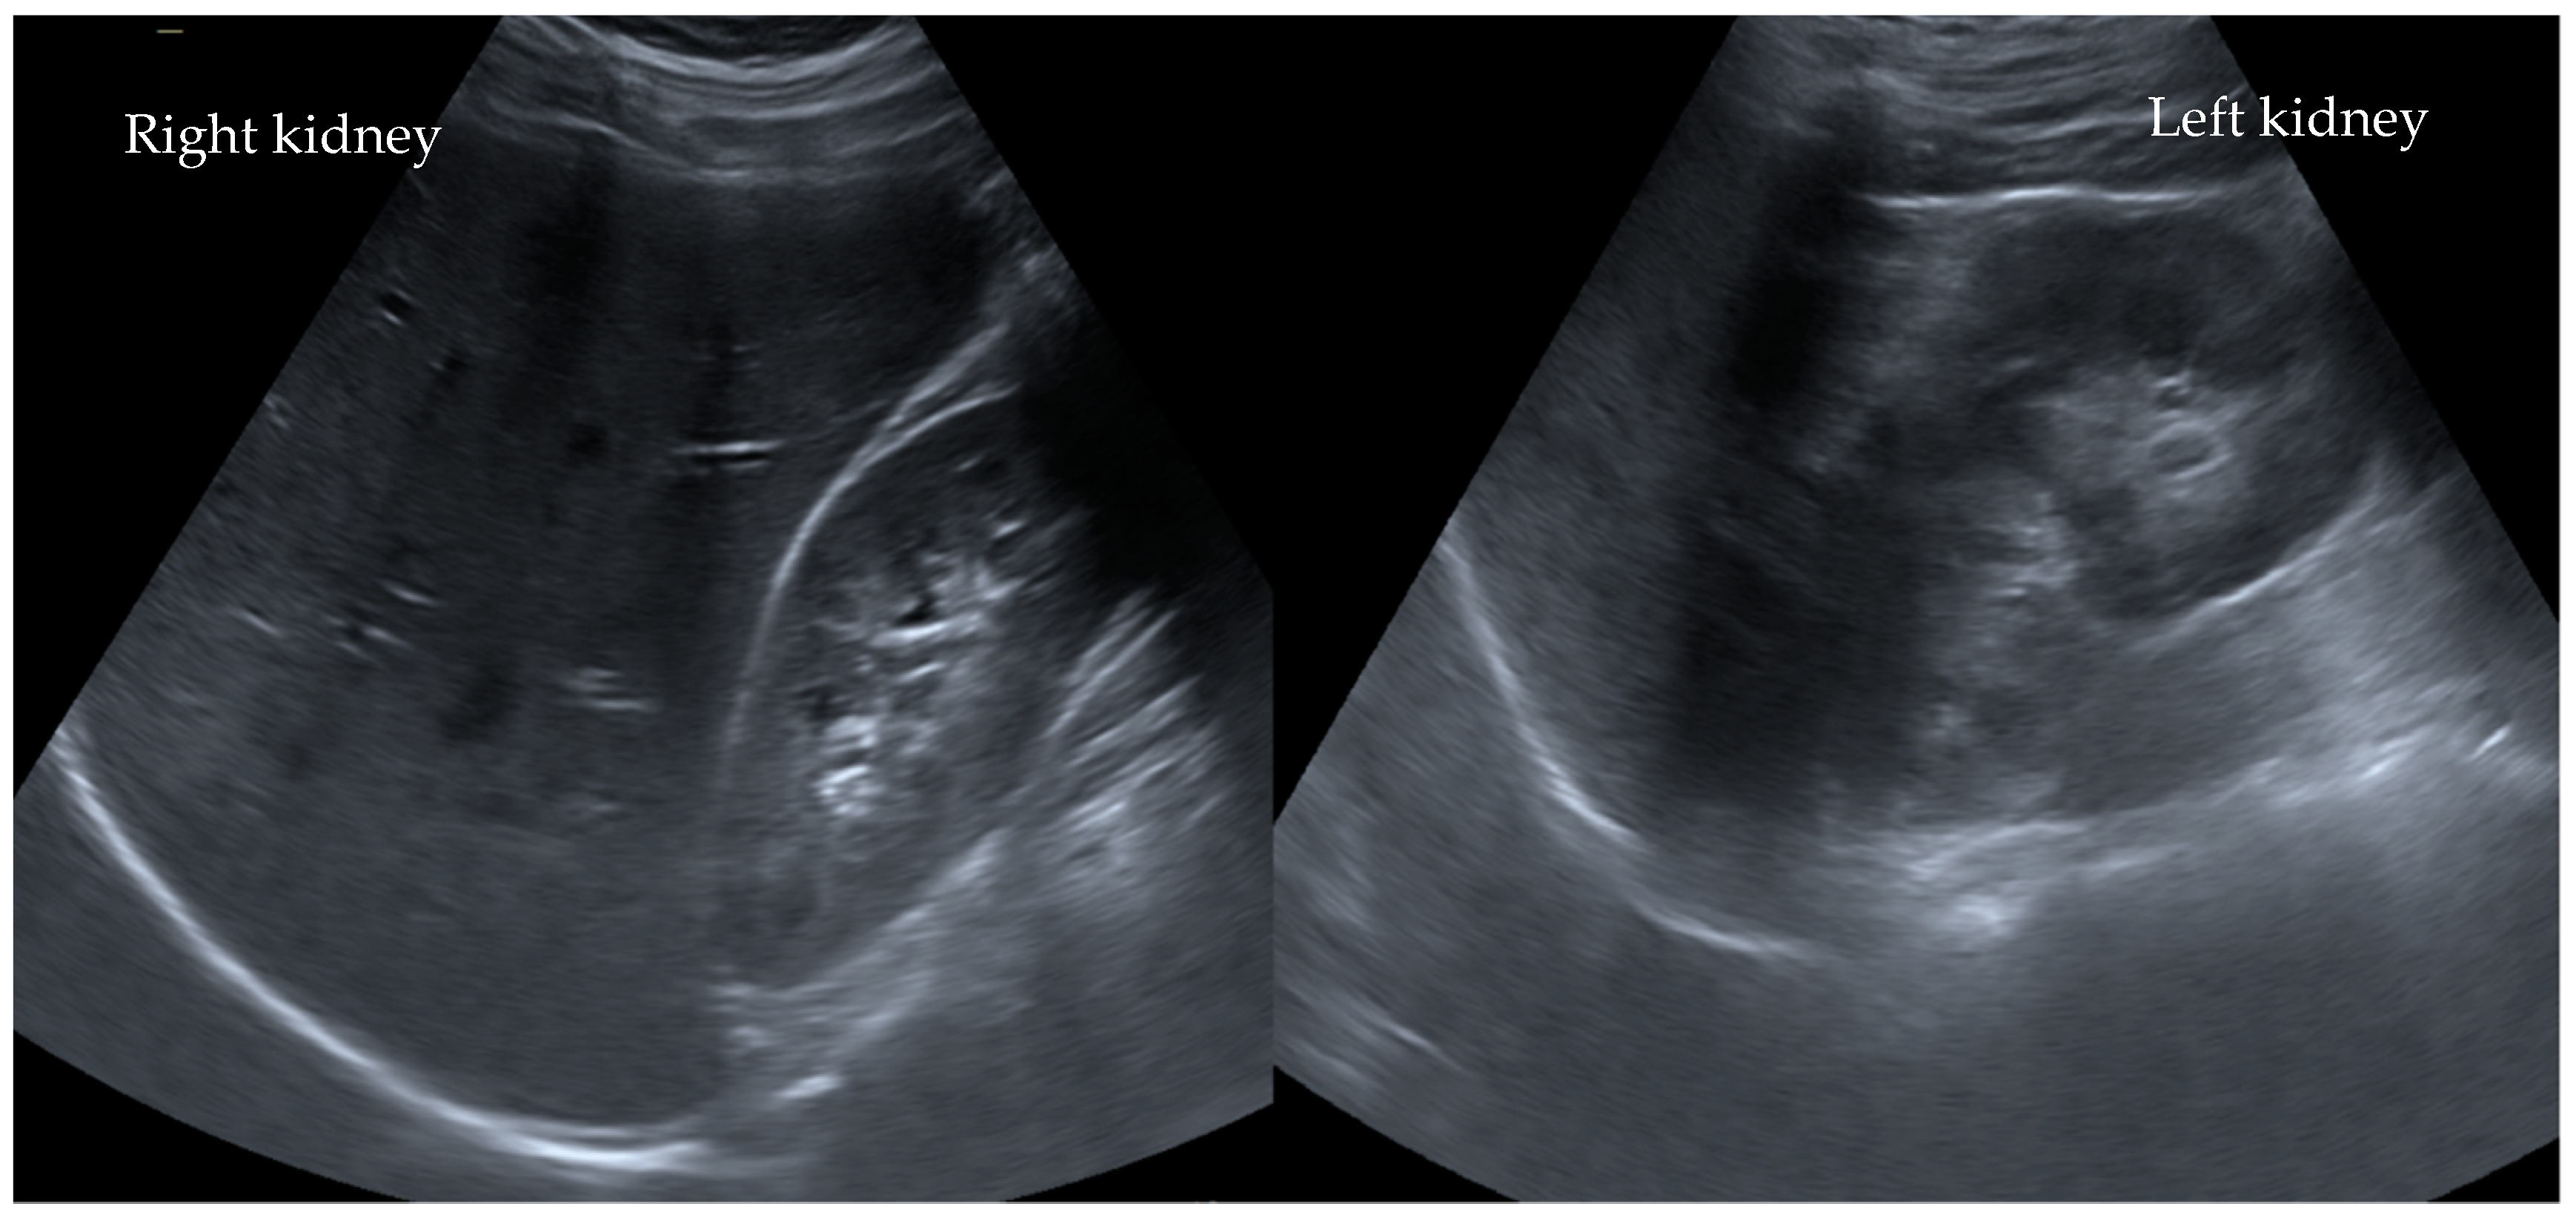

In addition, both potassium and C-reactive protein (CRP) levels were highly elevated at 6.3 mmol/L and 4.0 mg/dL, respectively. All other laboratory tests were within the normal range. Interestingly, an abdominal ultrasound revealed no abnormalities (Figure 1). Due to the suspicion of an acute abdomen, elevated inflammatory parameters, and an increase in serum creatinine to 3.1 mg/dL (stage failure according to pRIFLE), an ultrasonography of the abdomen (Figure 1) was performed. An MRI scan revealed slightly irregular signaling in the upper renal pole region on both sides in the context of possible interstitial nephritis (Figure 2).

Figure 1. No parenchymal pathologies observed ultrasonographically in the kidneys after ibuprofen misuse in Case I°. Ultrasonographically, there are no parenchymal changes, medullary pyramids, especially sonomorphologically laterally symmetrical and inconspicuous with good corticomedullary parenchymal differentiation. The kidneys are normal in size. The resistance index is laterally symmetrical and normal for age.